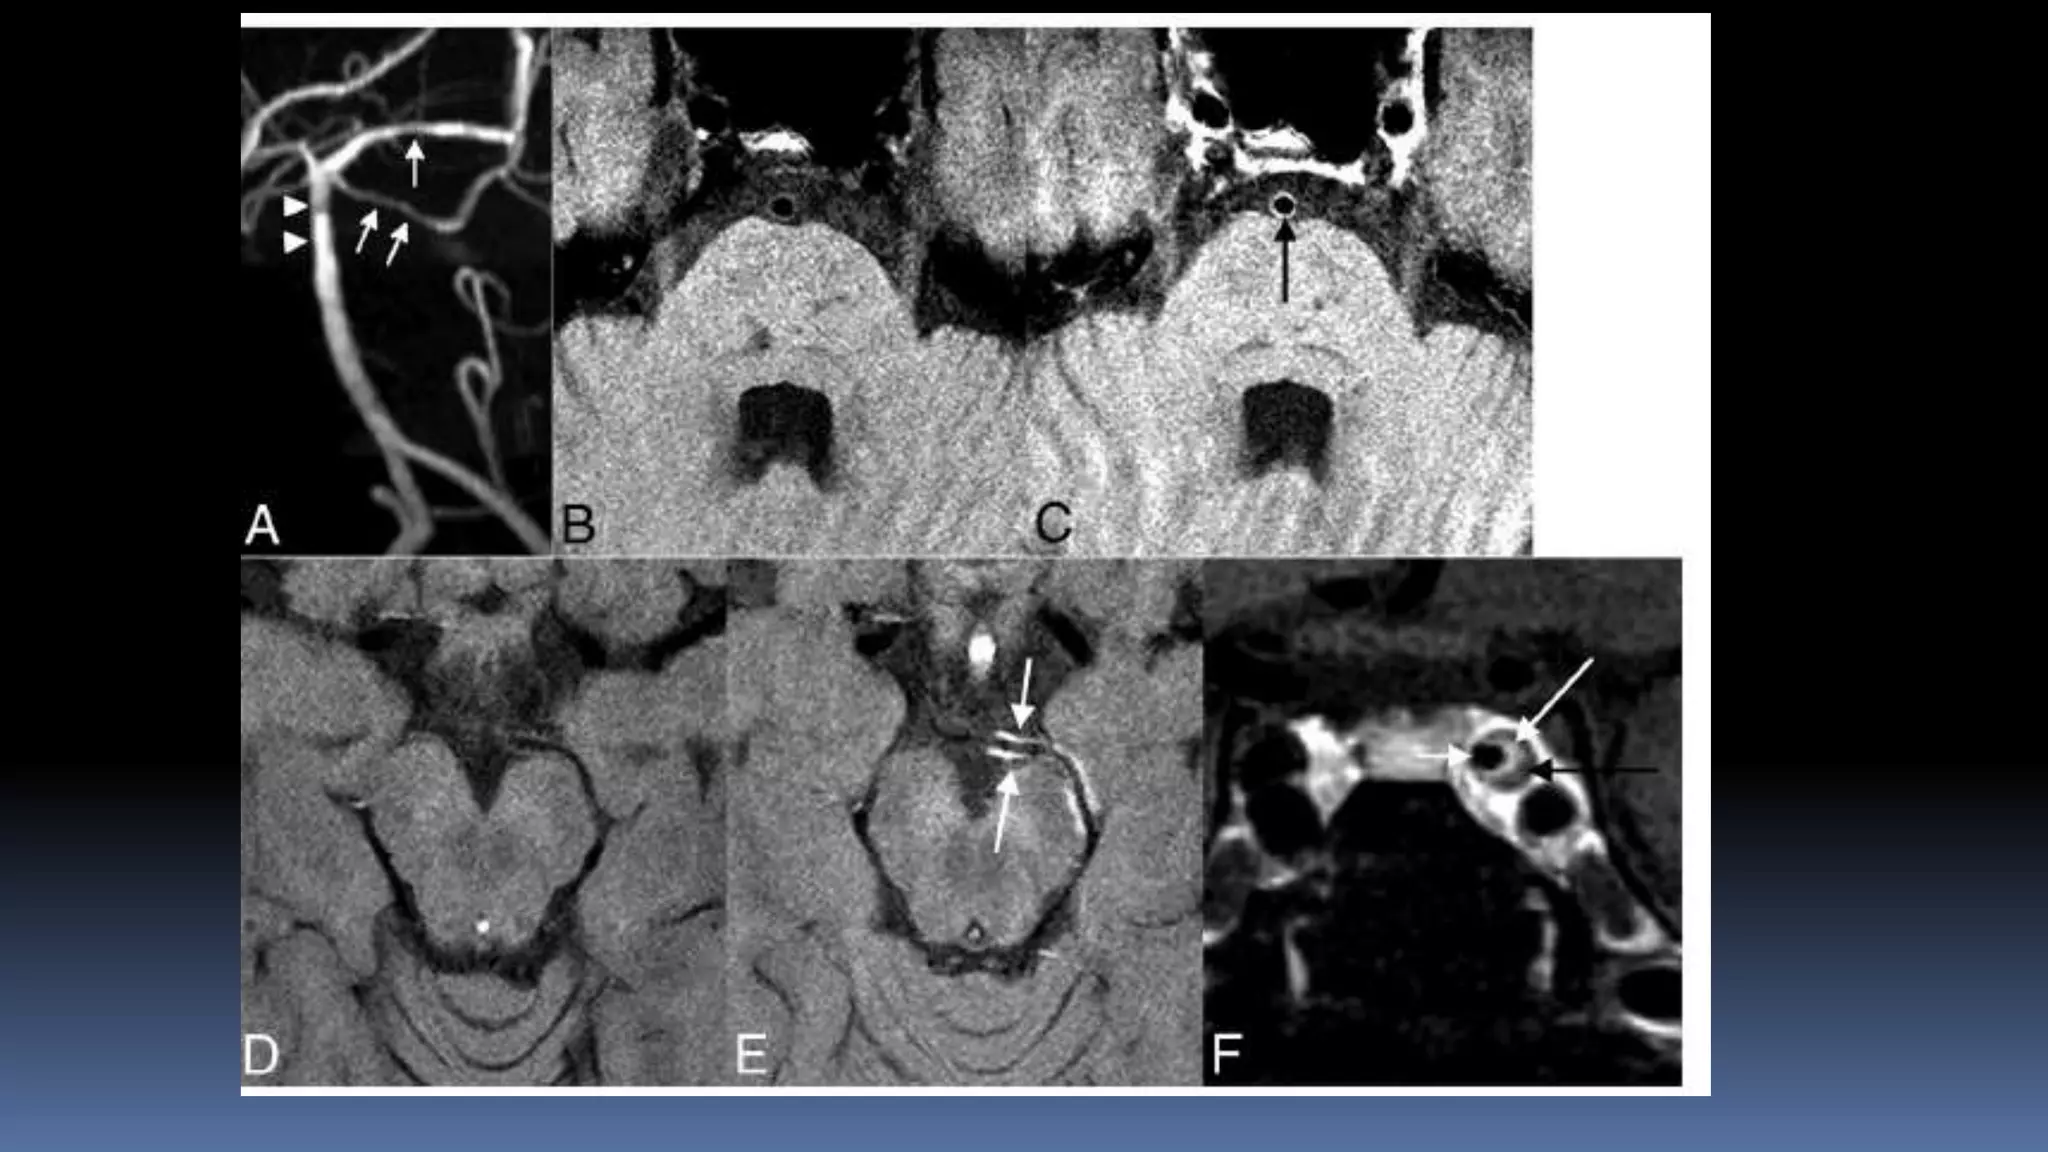

Vessel wall imaging

•MR vessel wall imaging is a powerful tool for extracranial (eg, carotid)

plaque characterization, enabling the determination of stroke risk from

carotid plaque rupture

•The Multi-Ethnic Study of Atherosclerosis carotid MR imaging study first

reported associations of carotid plaque features with future events. It

showed that the remodeling index and lipid core presence measured

on MR imaging added a risk for a new event beyond traditional risk

factors in individuals without a history of cardiovascular disease.

ICAD

Vessel wall imaging •MRvessel wall imaging is a powerful tool for extracranial (eg, carotid) plaque characterization, enabling the determination of stroke risk from carotid plaque rupture •The Multi-Ethnic Study of Atherosclerosis carotid MR imaging study first reported associations of carotid plaque features with future events. It showed that the remodeling index and lipid core presence measured on MR imaging added a risk for a new event beyond traditional risk factors in individuals without a history of cardiovascular disease.